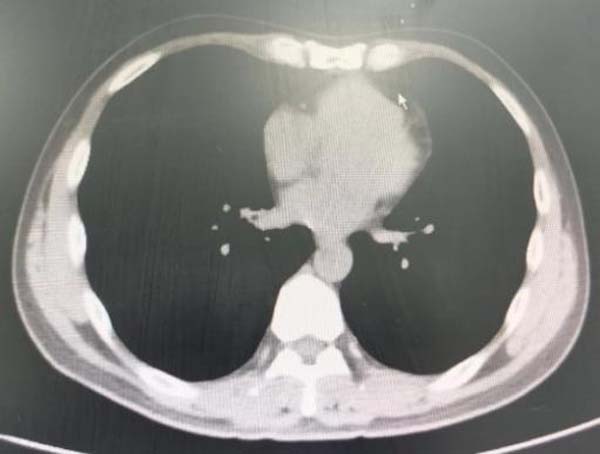

图3.胸部CT显示右肺下叶内基底段支气管结石影已消失

为检验手术效果,一周后,患者来到医院复查,胸部CT显示:气道内的石头消失得无影无踪。为表达救命之恩,患者特意送来一面锦旗,感激周云芝主任团队的高超医术及大医精神。